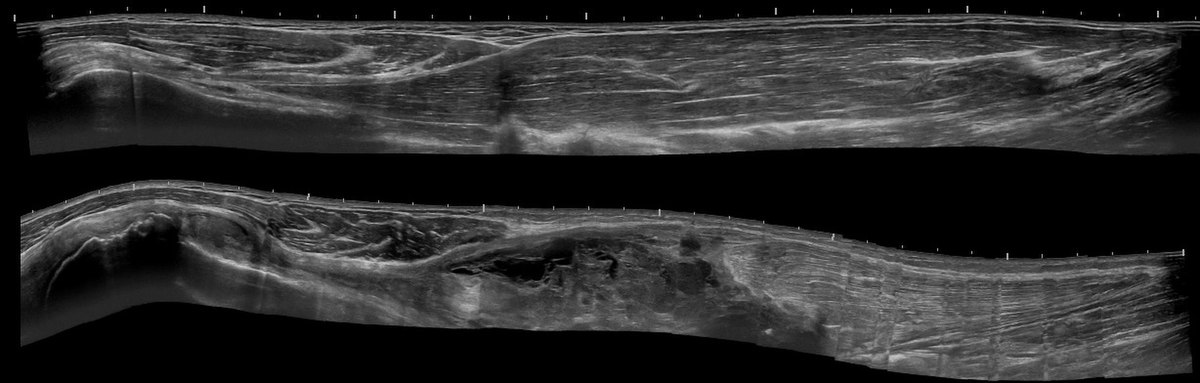

Ο ασθενής με ρήξη του καταφυτικού τένοντα του δικεφάλου χρειάζεται εκτίμηση από εξειδικευμένο Ορθοπαιδικό Χειρουργό. Ο κ. Βλάχος αφού λάβει το ιστορικό σας και σας εξετάσει πολύ προσεκτικά, θα πραγματοποιήσει υπερηχογράφημα με σκοπό να ελέγξει την ακεραιότητα ή μη του τένοντα. Σε συγκεκριμένες περιπτώσεις ο ιατρός θα χρειαστεί να σας παραπέμψει για μαγνητική τομογραφία και απλή ακτινογραφία.